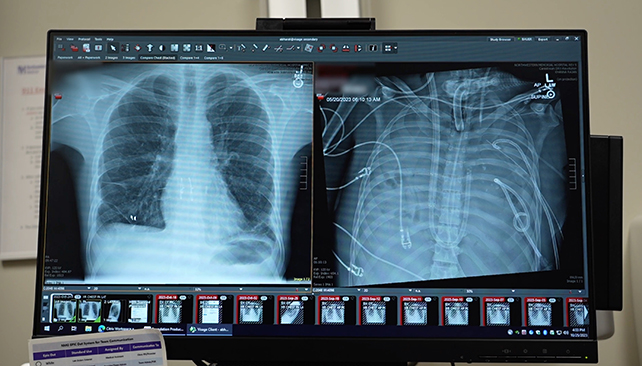

It's a story that starts in spring 2023, when the 33-year-old man developed influenza-associated lung failure. This rapidly progressed to pneumonia, sepsis, and what's known as acute respiratory distress syndrome (ARDS).

"He had developed an infection of his lungs that just could not be treated with any antibiotics because it was resistant to everything," says thoracic surgeon Ankit Bharat.

"That infection caused his lungs to liquify and then continued to progress to the rest of his body."

The standard approach would be to put the patient on a life support system and give the lungs time to recover. Here, though, the lungs were the main problem and source of infection: The man seemed certain to die if his lungs weren't removed, and very likely to die if they were.

Bharat and his team carried out a molecular analysis of the lungs after they'd been removed, confirming that there was no chance of the lungs recovering from ARDS of their own accord.

The scarring and immune damage meant that in this case, a lung transplant was absolutely necessary.